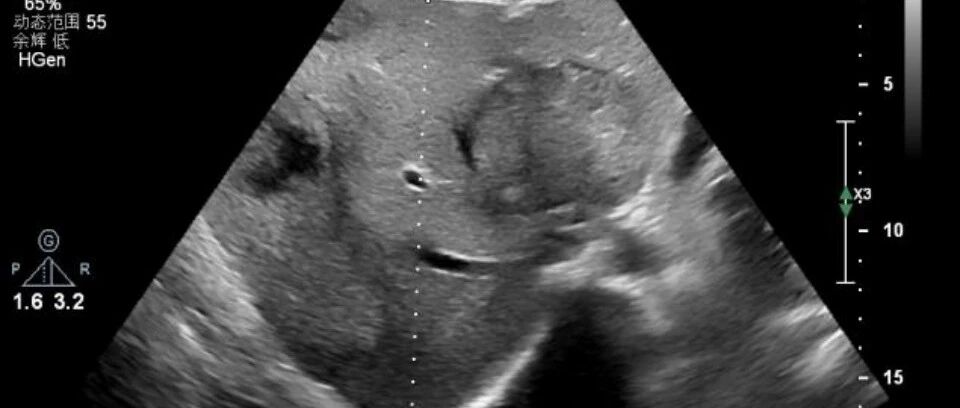

这个病例是子宫肌瘤还是内膜异位?其实都不是! 丁香园超声时间 · 公众号 · 医学 · 1 年前 · |